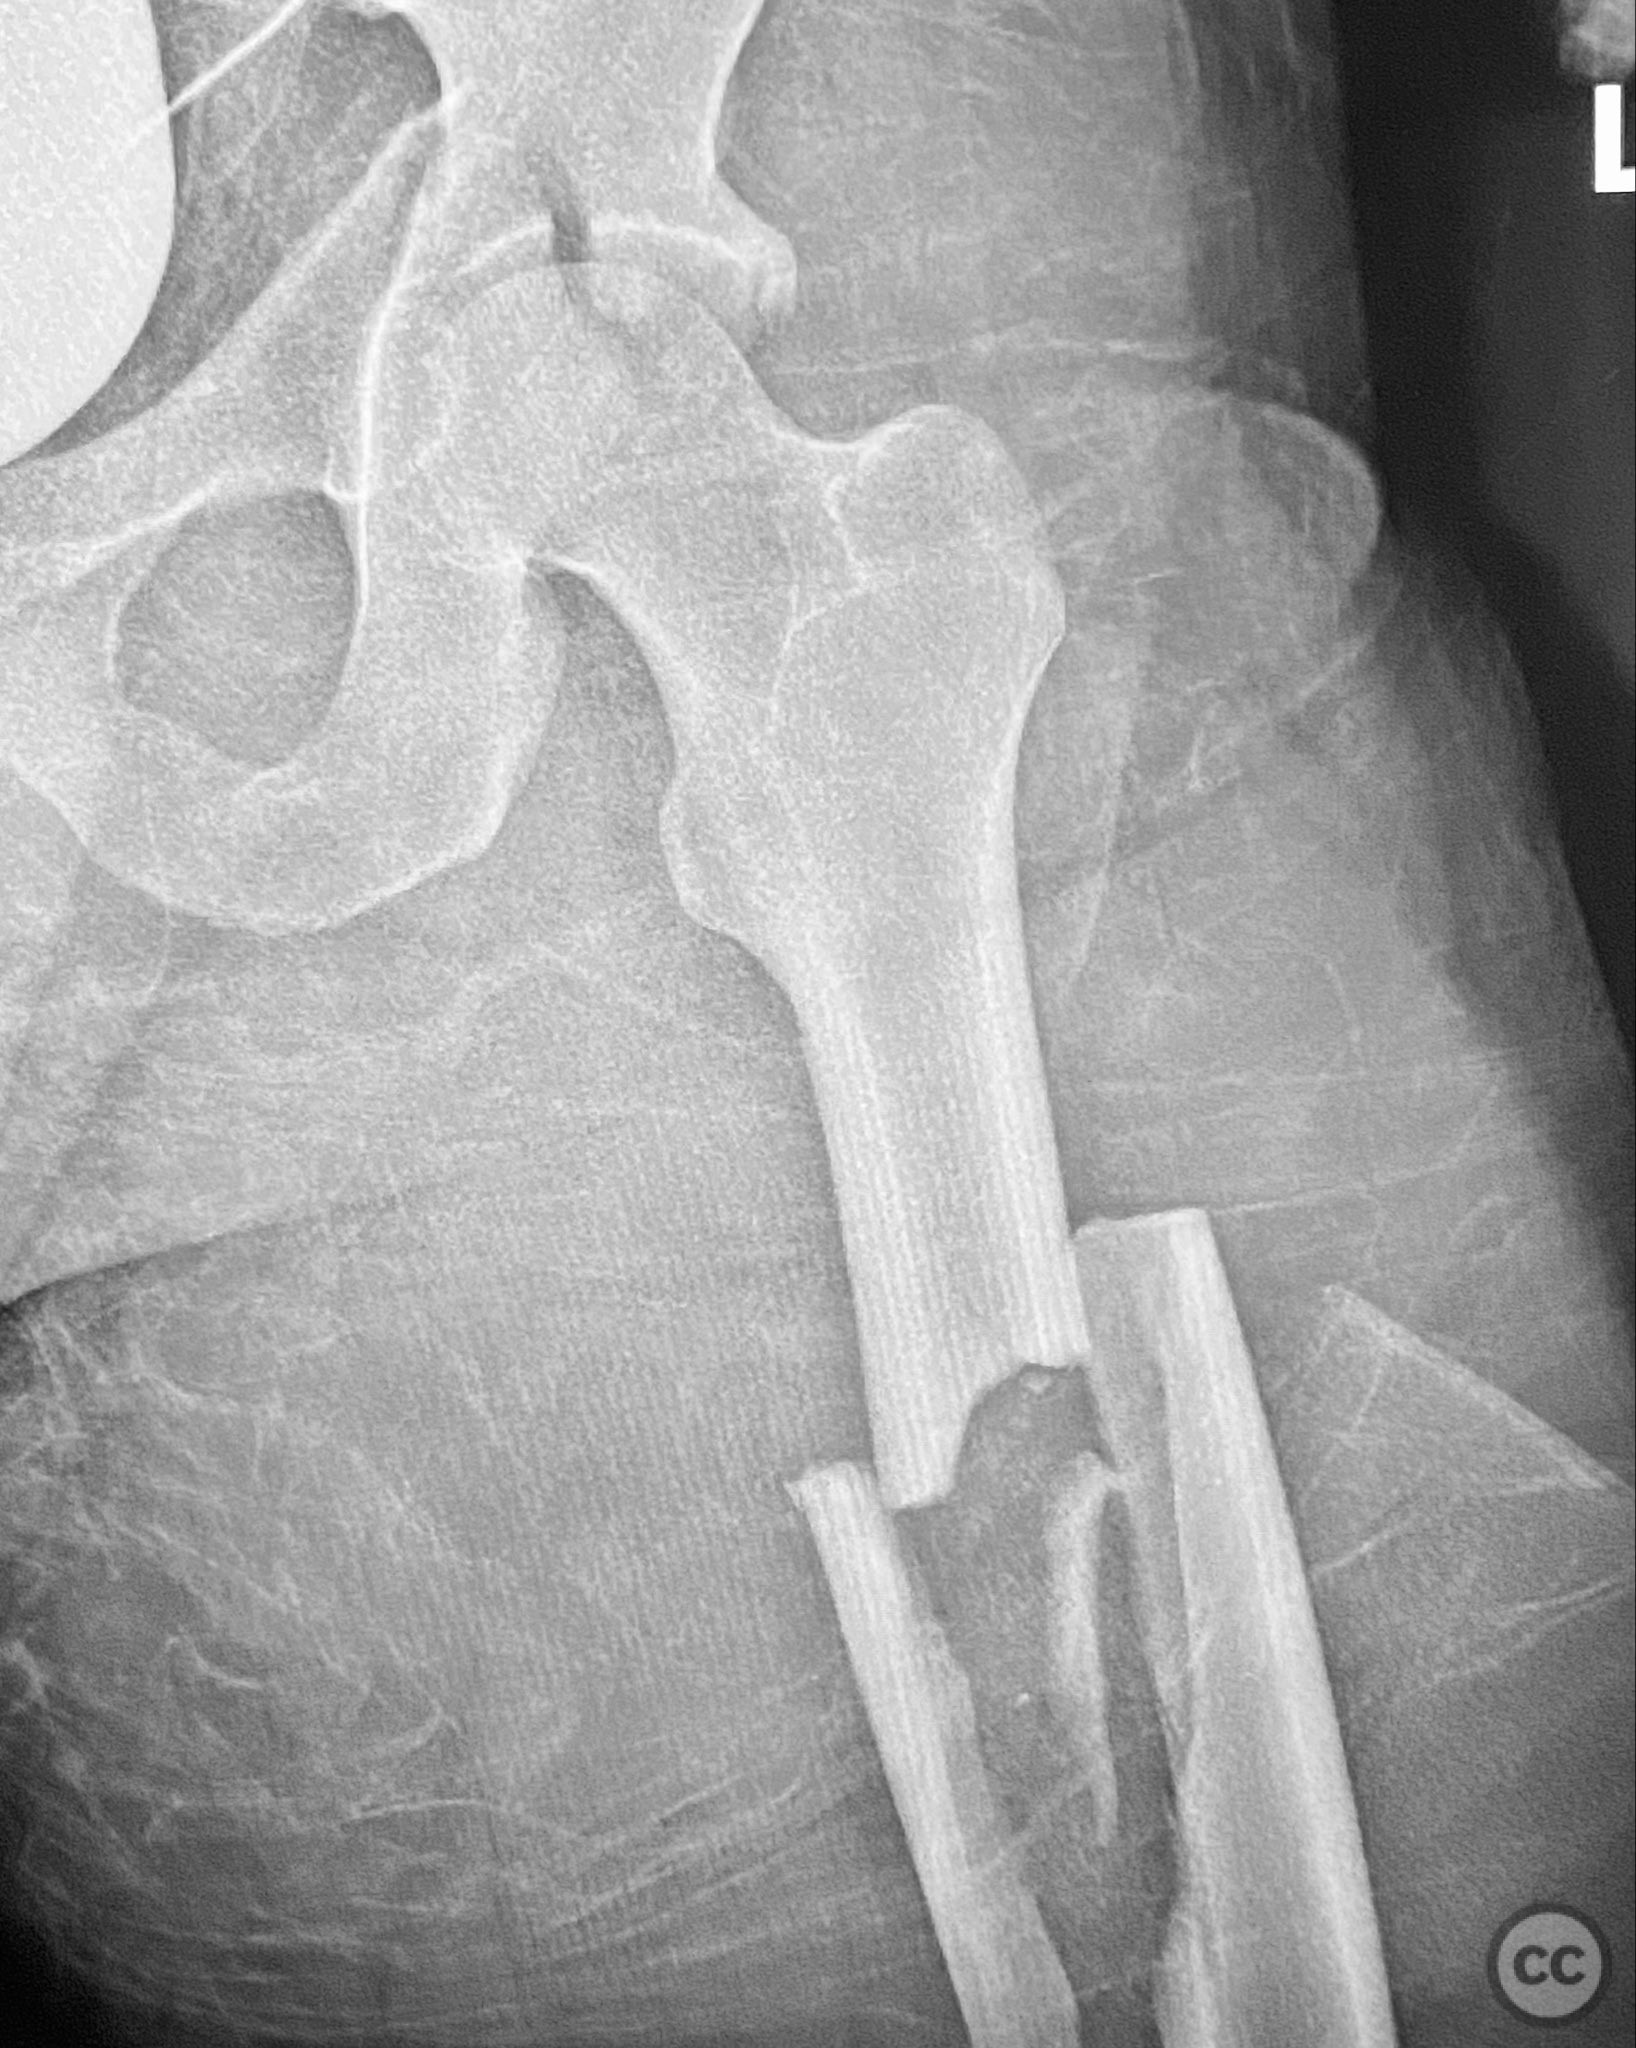

Uploaded on Dec 08 2025

Ipsilateral Tibial Shaft and Trimalleolar Ankle...

• Case by Seçkin Doğan

- Turkey